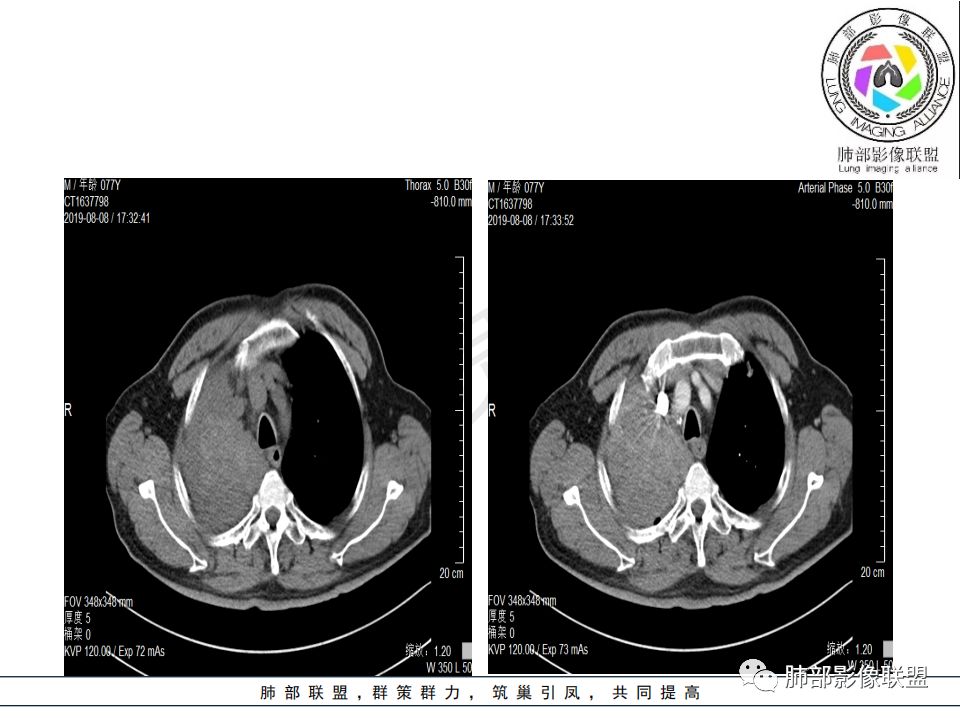

右肺主支气管有软组织肿块,向腔内外生长,右肺上叶肺不张,边缘光滑,增强扫描不均匀强化。考虑恶性肿瘤,鳞癌可能。

晨读,右肺主支气管有阻塞,腔内.腔外都见软组织影,右肺上叶不张,肿块内部密度不均匀,是不是有坏死影,老年男性,考虑恶性~鳞癌

右肺主支气管内外软组织影,支气管变窄截断,右肺上叶成软组织密度,其内见细沙样钙化,周围看见小结节,右肺门看见一淋巴结稍大,增强不均匀强化,胃癌病史,考虑:转移,或原发肺恶性鳞癌。

晨读病例:老年男性,症状轻,右侧胸廓略塌陷,右肺主支气管内外软组织影,支气管变窄截断,右肺上叶不张,其内见细砂样钙化,周围看见小结节,右肺门看见一淋巴结稍大,增强不均匀强化,胃癌病史,常规考虑:转移,或原发肺恶性鳞癌。鉴别支气管TB?

从强化情况和冠状位看主要还是从外向内的一个肿块,有不张,但不张范围不大,近端支气管堵塞,考虑腺癌或类癌(原发或转移都可能),鉴别鳞癌。